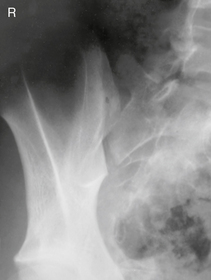

Lateral cervicothoracic (swimmer’s) (R)

Swimmer’s (Twining Method) C5-T3 Region

• Erect preferred, align C-spine to CR (and centerline of IR).

• Elevate arm and shoulder closest to IR and rotate this shoulder slightly anteriorly or posteriorly.

• Opposite arm down, relax and depress shoulder, with slight opposite rotation (from other shoulder) to separate humeral heads from vertebra. May also be taken in lateral recumbent position with one arm and shoulder down and one up—Pawlow method.